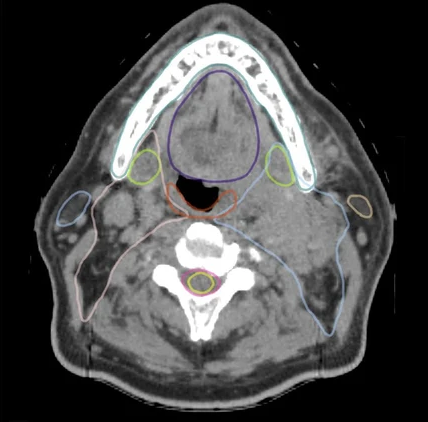

由 RefleXion X1 生成的未经编辑的头颈图像显示出出色的对比度和细节分辨率,并且在多个结构上可见近乎完美的 Limbus AI 轮廓。

这种整合将减少患者在治疗计划过程中最重要的瓶颈,其中包括将肿瘤靶标与周围的关键器官和其他健康组织区分开来。根据治疗计划的复杂程度,预计轮廓修整时间最多可减少 80%,从而确保患者得到及时治疗。

放射治疗计划从患者对肿瘤靶点进行计算机断层扫描 (CT) 成像开始。然后,临床医生手动勾画或“勾勒出”治疗区域和应尽量减少照射的附近器官(称为危险器官或 OAR)的轮廓。这种手动过程非常耗时,并且临床医生之间常常存在差异,这可能导致治疗计划质量不一致并限制其有效性。

Limbus Contour采用经过临床验证的深度学习分割算法,具有高精度,可减少人为错误,并有助于确保精确地将辐射输送到目标区域并避免 OAR。

“Limbus Contour 软件的性能取决于 CT 图像的质量,”Limbus AI 首席执行官 Karl Otto 博士说。 “X1 图像具有高分辨率、出色的对比度以及最小的噪声和运动伪影。这将提高区分相邻结构的精度,并产生一致、可靠的轮廓结果,确保患者获得尽可能最高质量的护理。”